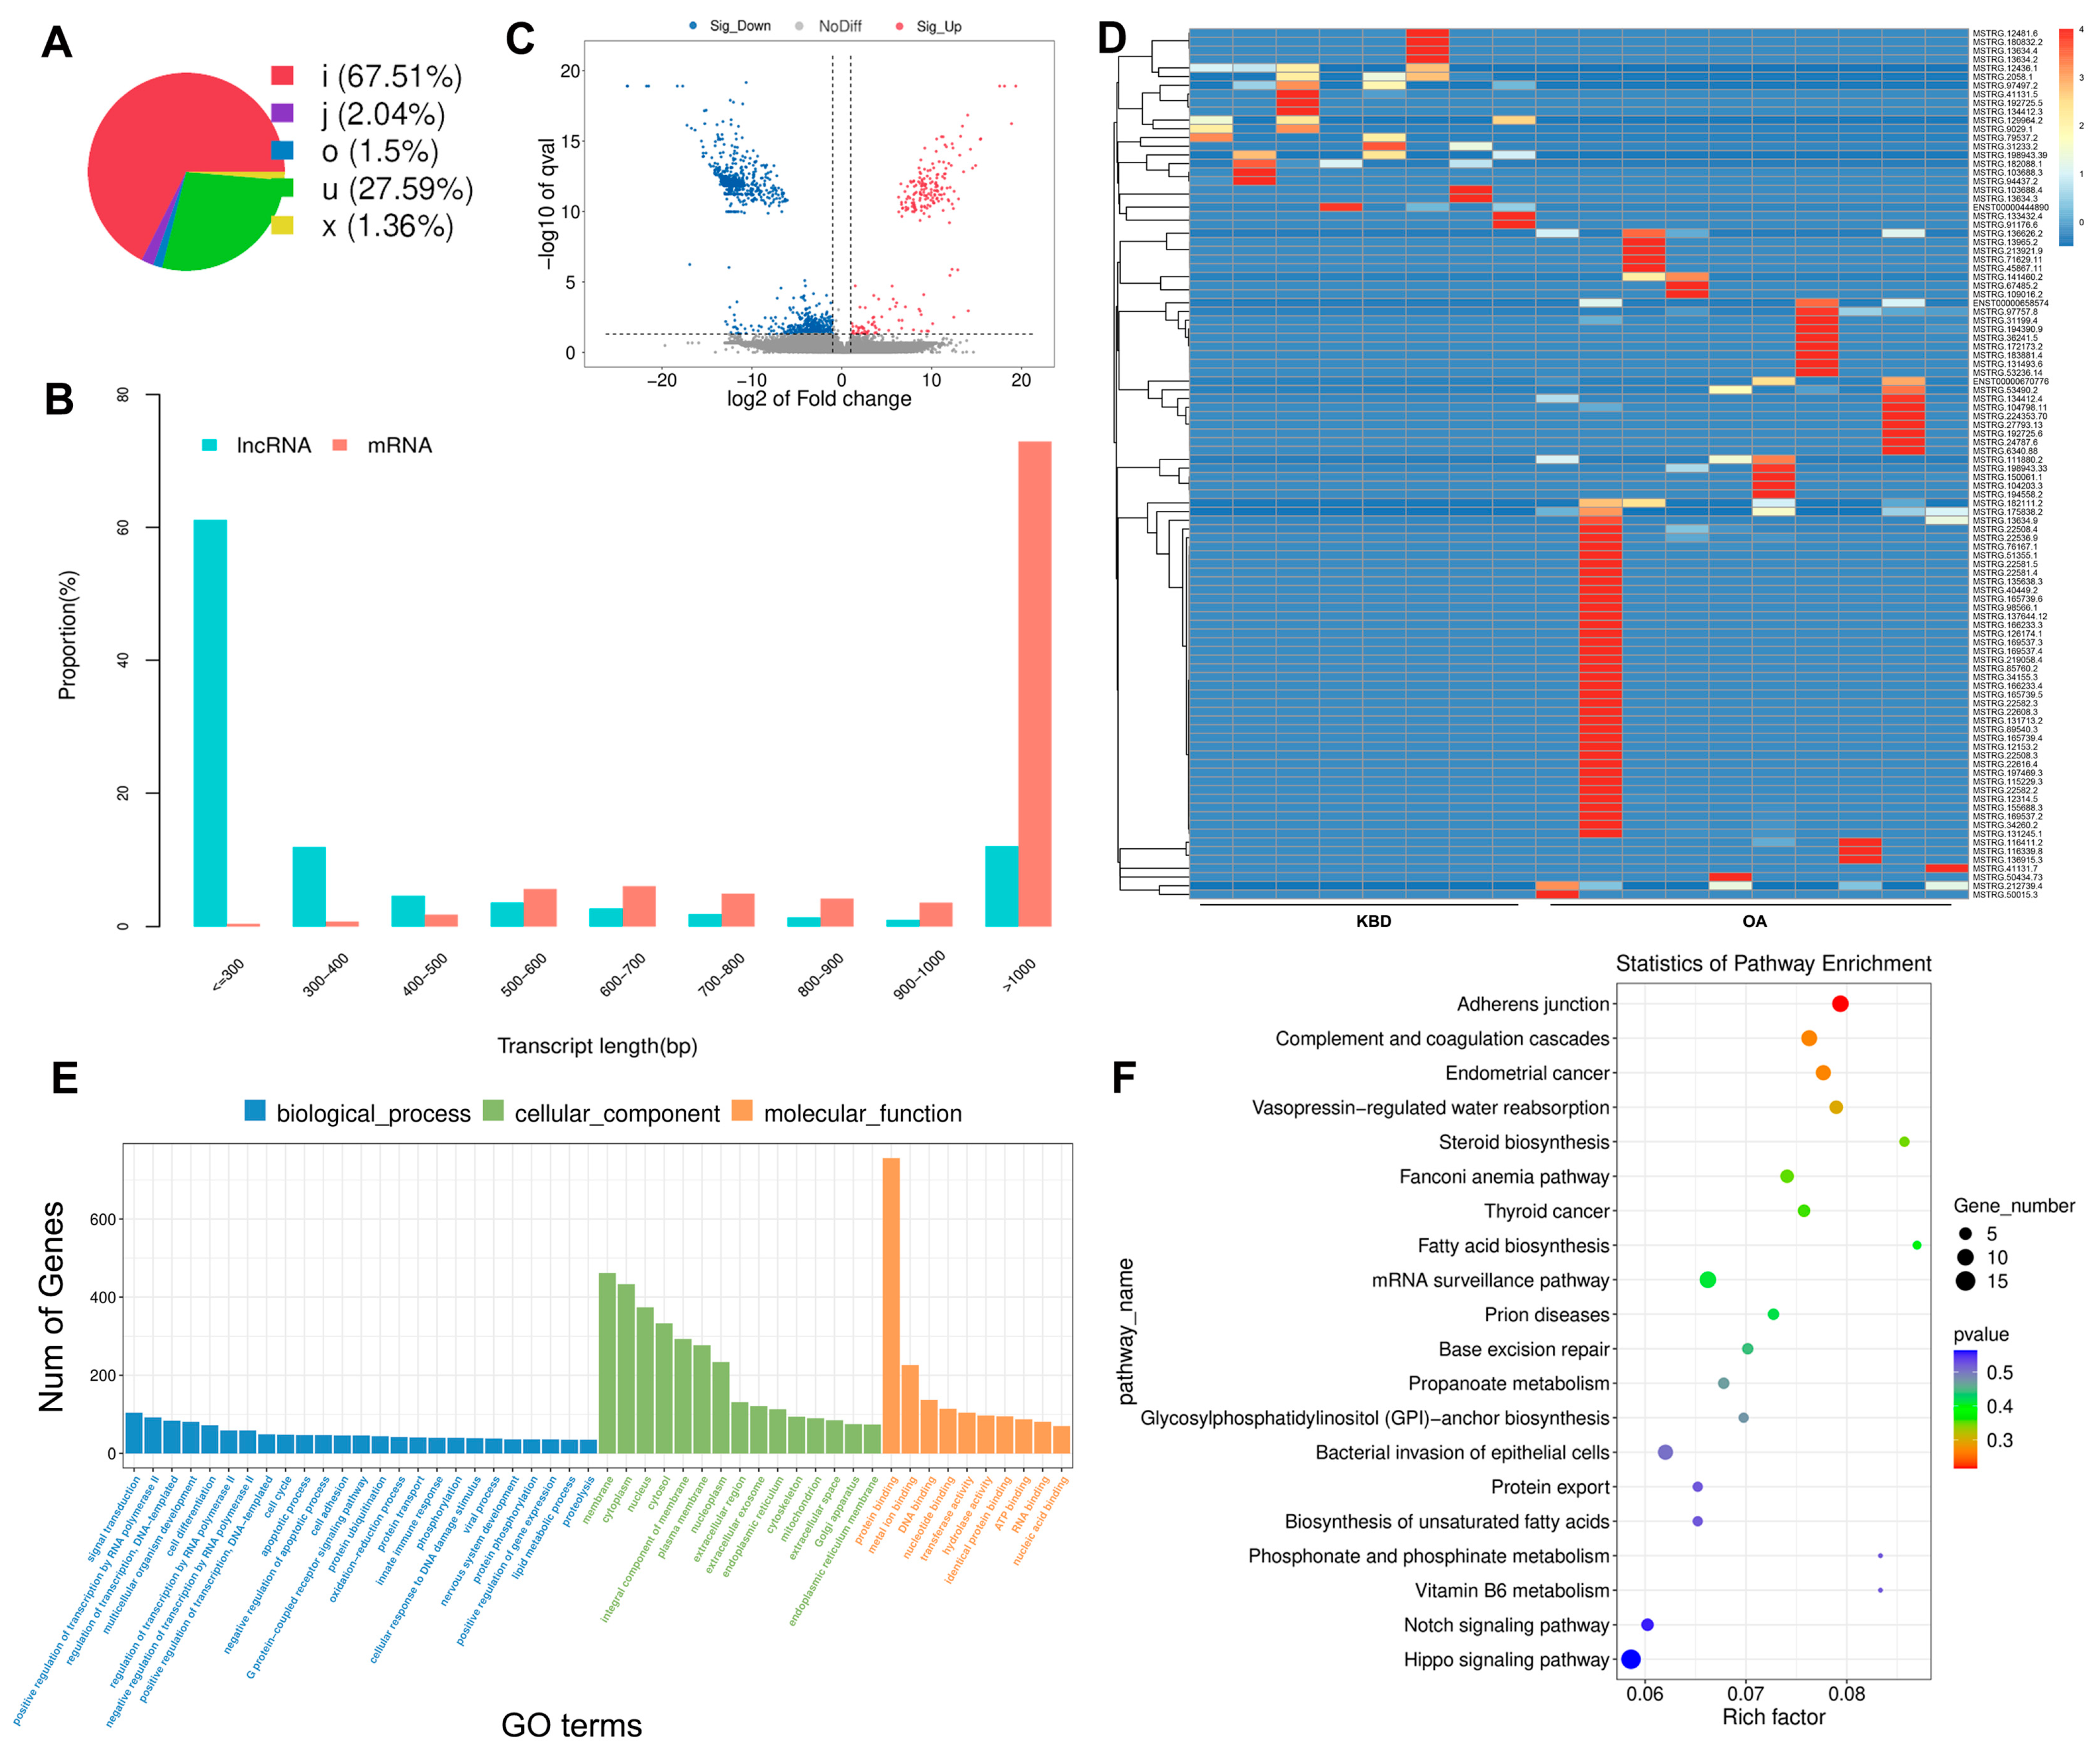

2.2. Identification of DE mRNAs between KBD and OA

2.3. Prediction and Function Analysis of the lncRNA Target Genes

2.4. Overview of the circRNA Sequencing Data